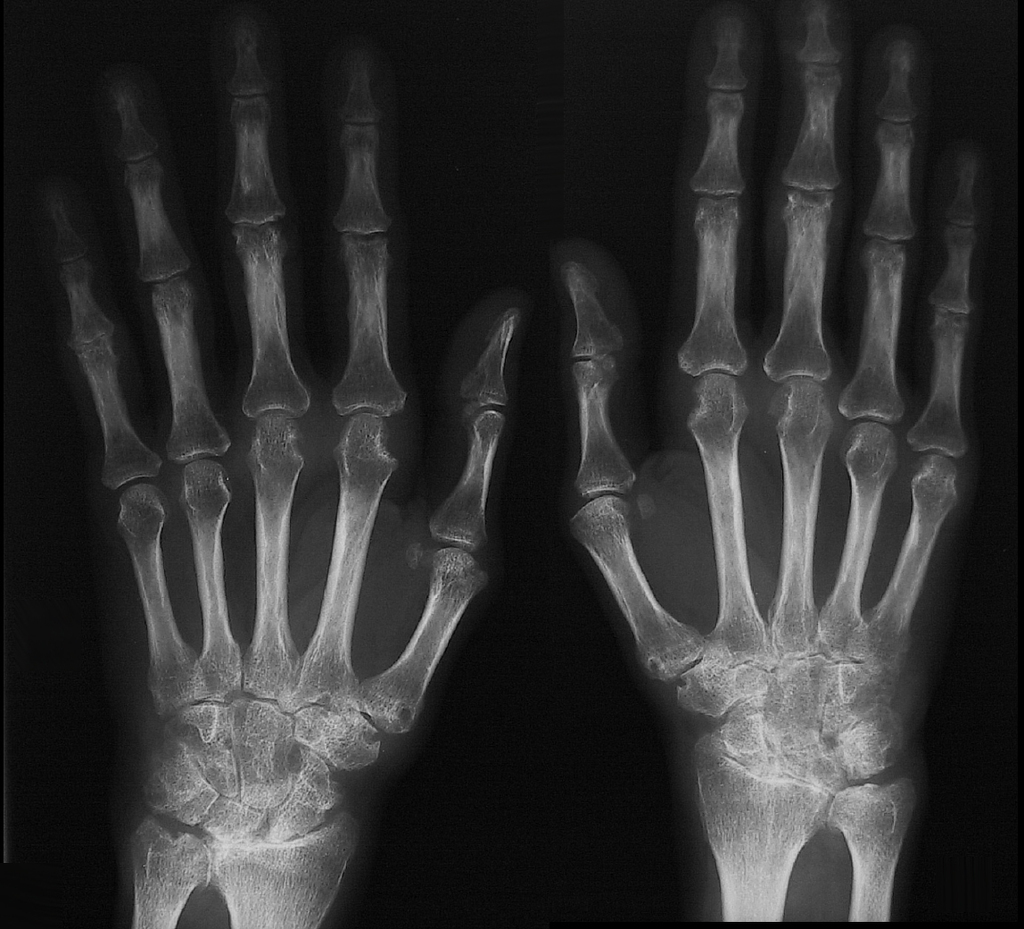

erosion in RA occur where in the joint?

Marginal erosions at the “bare area”

What is the “bare area”?

region of exposed bone just within the joint capsule that is not covered by thick cartilage

Type of joint space narrowing in RA

symmetric joint space narrowing